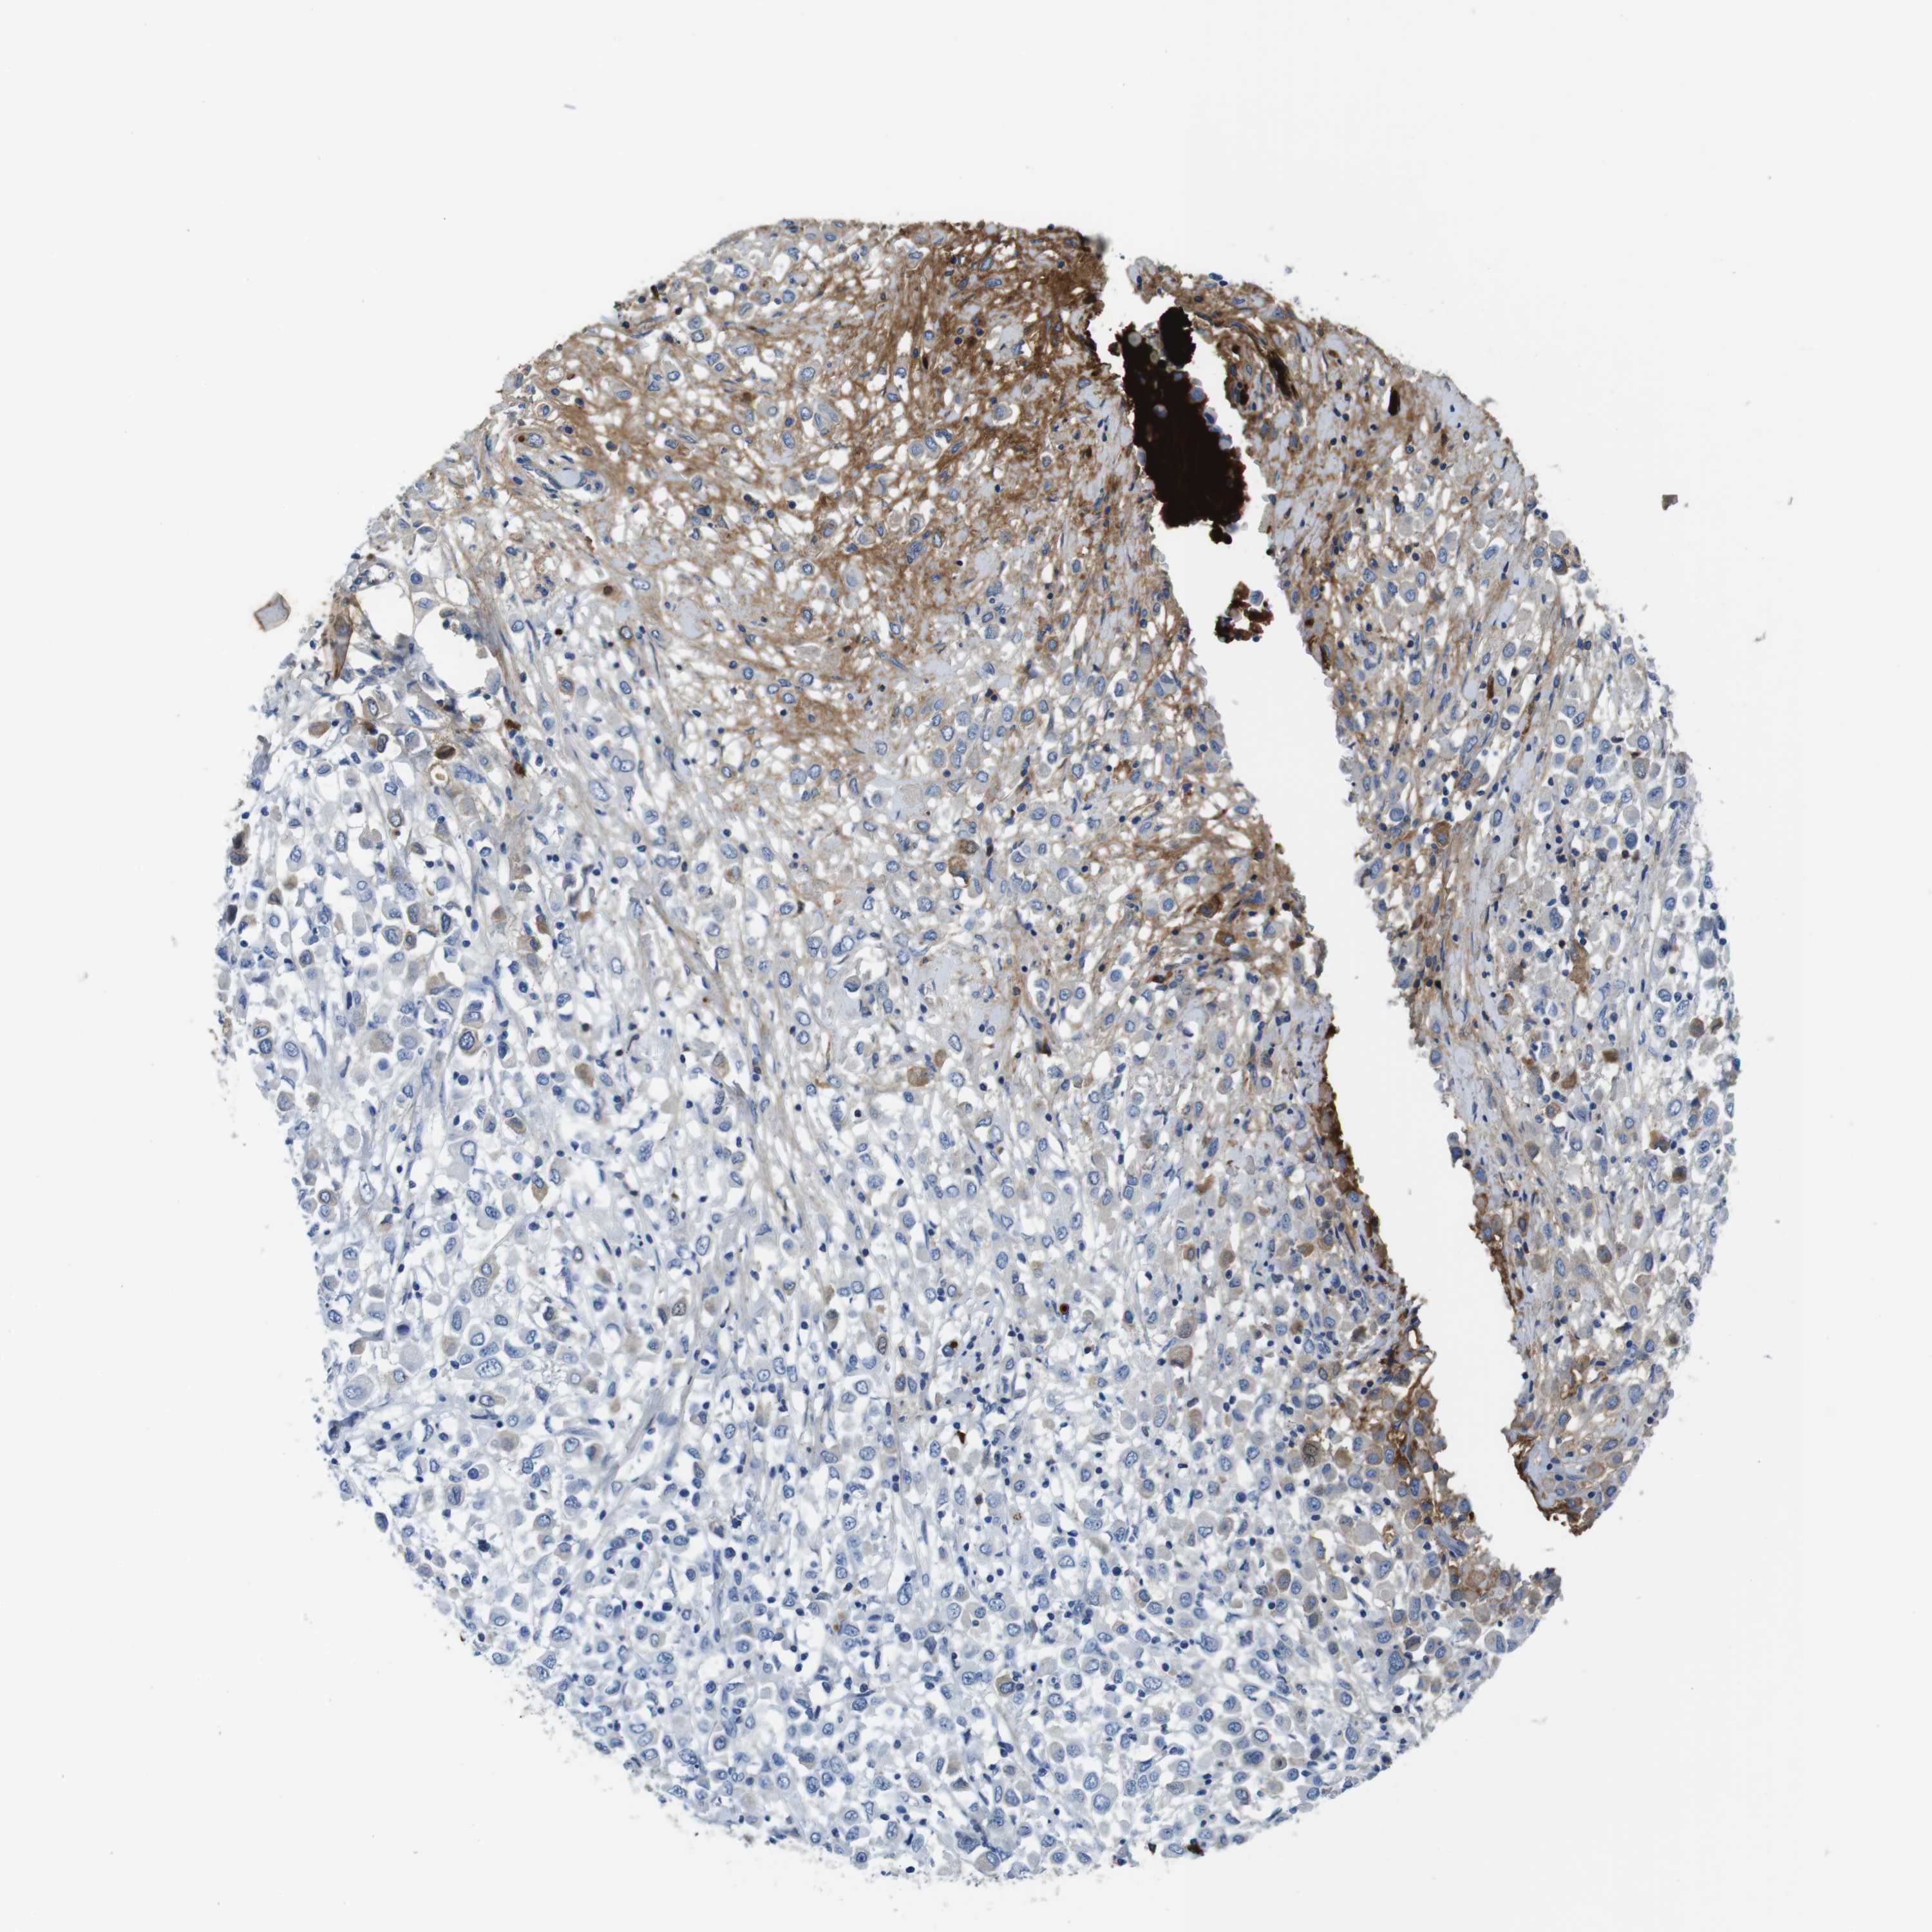

CANCER BREAST CANCER Show tissue menu

BRCA TCGA BRCA VALIDATION PROTEIN EXPRESSION

IGKC is potential prognostic, high expression is favorable in Breast Invasive Carcinoma (TCGA)